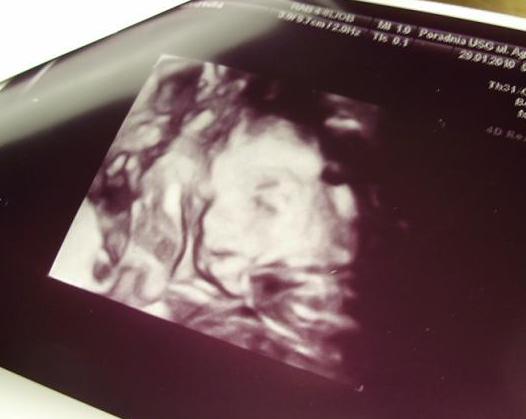

cudeńko